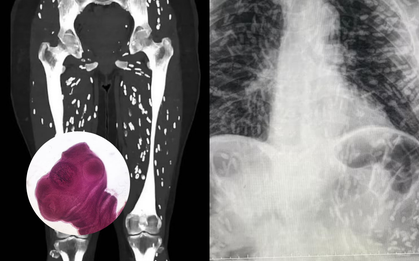

Người đàn ông bị đau hông, bác sĩ phát hiện ra bí mật đáng sợ

Sau khi than phiền về cơn đau hông, người đàn ông giấu tên đã đến bệnh viện để chụp chiếu định kỳ và bác sĩ đã phát hiện ra bí mật đáng sợ bên trong cơ thể anh ta. -

Sán làm tổ khắp bên trong người, tất cả do một kiểu nấu thịt lợn nhiều người Việt thường xuyên mắc phải

Hình ảnh bên trong cơ thể một người mắc sán dây lợn khiến nhiều người không khỏi hoang mang.